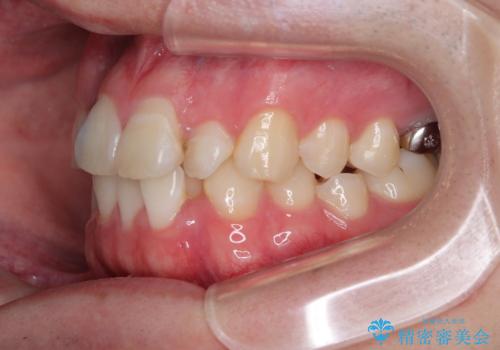

初診時の状態

・上下ともに歯がきれいに並びきらず、がたつきが見られました。

・上下の前歯の中心(正中)がずれています。

・特に上顎の幅が狭いため、下顎の歯列も内側に入り込み、歯が並ぶスペースが不足していました。